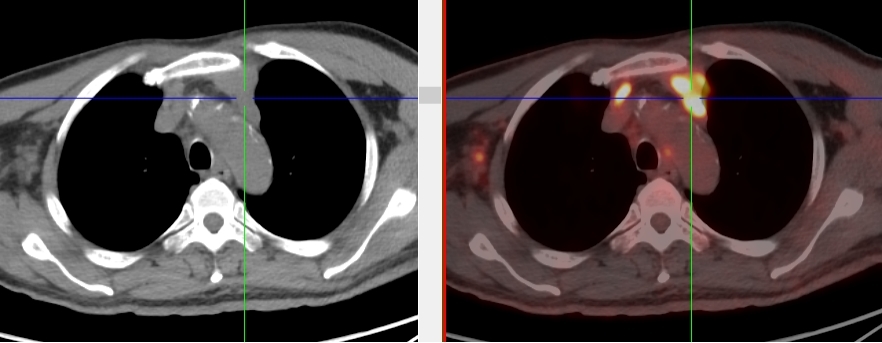

完善PET/CT檢查示:右側(cè)腋窩、雙側(cè)中下頸部、縱隔、雙側(cè)肺門多發(fā)MT,建議淋巴結(jié)活檢。后患者行右腋窩淋巴結(jié)切除活檢術(shù),經(jīng)北京大學(xué)第三醫(yī)院病理科會診示:右腋窩淋巴結(jié)惡性腫瘤,呈淋巴竇內(nèi)生長模式,瘤細(xì)胞呈上皮樣,異型性明顯,伴中性粒細(xì)胞浸潤。結(jié)合病史及免疫組化,考慮為SMARCA4(BRG1)缺失的胸部腫瘤,伴神經(jīng)內(nèi)分泌標(biāo)記表達(dá)。

本例為罕見病理類型的腫瘤,影像學(xué)表現(xiàn)無明顯特異性,診斷困難。強(qiáng)化CT和穿刺病理已基本明確為惡性腫瘤,行PET/CT檢查一是為了全身檢查,完善分期,二是根據(jù)PET代謝情況指導(dǎo)進(jìn)行生物靶區(qū)活檢,進(jìn)一步明確病理診斷。最終,PET/CT除縱隔病變外發(fā)現(xiàn)更多頸胸部淋巴結(jié)代謝異常,綜合考慮后對腋窩淋巴結(jié)進(jìn)行切除活檢,最終得到病理證實(shí)。